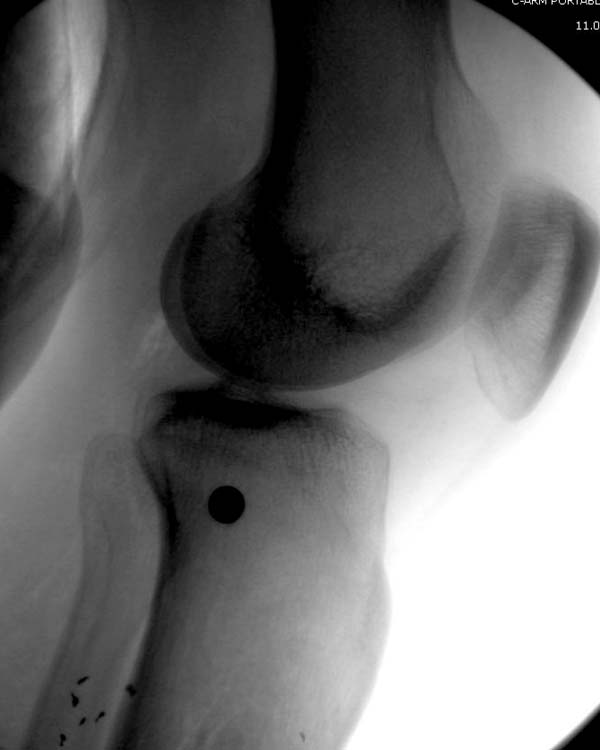

У моего б-го обширна ран по всей передней половине с/3 голени, в основном гранулирует, но область перелома по передне-медиалной поверхности открыта 2 на 2 см

Вид покачественне

Вопрос: у вас рубец в в/3 голени - это "случайно" не интармедуллярный гвоздь стоит?

Спасибо, Др.Дмитриев! Да у Вас просто орлиный глаз! :)) Действительно, там гвоздь без рассверливания, ведь перелом был закрытый. Я думаю, некроз пошел от удара бампером автомибиля

И в ране видна область перелома. Трепанации так близко к перелому не навредят? Кровушки вакуумом слишком не потеряем из костнмозгового? Как насчет гвоздя и вакуума?

Снимки от 23-го июня

23-е июня